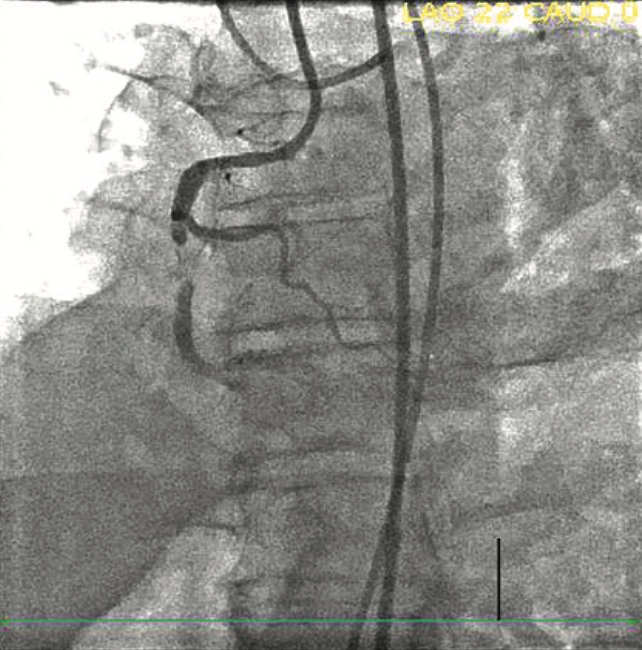

A Corsair Pro microcatheter (Asahi Intecc) was brought antegrade initially with a Gladius Mongo wire (Asahi Intecc); the wire crossed the proximal cap but entered the subintimal space. Both a Pilot 200 (Abbott Vascular) and Hornet 14 wire (Boston Scientific) failed to enter the true lumen distally. A Mongo wire was then advanced with a knuckle fashion to the distal landing zone, followed by the Corsair Pro microcatheter. The Mongo wire was removed and replaced with a Miracle 12 wire (Asahi Intecc), followed by removal of the Corsair Pro and placement of a Stingray balloon (Figure 2). The Miracle 12 wire was removed and a Hornet 14 wire was used to reenter the vessel. Subsequently, the Hornet 14 was removed and swapped for a Pilot 200 wire, which was advanced into the true lumen distally and confirmed on retrograde injection. The Stingray balloon was removed and replaced with a Corsair Pro microcatheter. The Pilot 200 was removed and replaced with a Sion Blue (Asahi Intecc). The Sion Blue was used to wire the distal posterior descending artery (PDA). The Corsair Pro microcatheter was removed. The RCA was pre-dilated with a 3.5 noncompliant balloon, followed by intravascular ultrasound (IVUS). After IVUS, the RCA was stented with 4.0 mm x 38 mm, 4.0 mm x 38 mm, and 4.0 mm x 32 mm Synergy drug-eluting stents (Boston Scientific), all of which were post-dilated with a 5.0 noncompliant balloon. Repeat IVUS showed no edge dissection and good stent apposition. Final angiography showed no residual stenosis (100% to 0%) and TIMI-3 flow distally (Figure 3, Video 2).

Perclose devices (Abbott Vascular) were deployed at both access sites for hemostasis. The patient had 467 mGy radiation dose and fluoro time was 22.4 minutes. The cine dose was 5331 DAP uGym2. The total contrast (Omnipaque 350 [GE Healthcare]) used for the procedure was 100 mL.